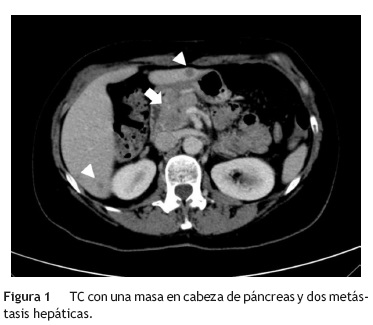

Mujer de 54 años que acudió al servicio de urgencias por dolor epigástrico agudo, astenia y pérdida de peso no cuantificada. Entre sus antecedentes personales destacaban: fumadora de 30 paquetes/año y consumo de alcohol de 50 gramos/semana; hipotiroidismo, y colecistectomía laparoscópica por pólipo vesicular benigno de 12 mm, sin litiasis en la pieza quirúrgica. Su historia familiar únicamente incluía la muerte de un hermano por cáncer de pulmón de estirpe histológica desconocida. En la exploración física se objetivó el dolor epigástrico sin otras anormalidades. En las determinaciones de laboratorio destacaban niveles elevados de amilasa (444 U/L), lipasa (1496 U/L) y proteína C reactiva (9 mg/dL), con valores normales de los marcadores tumorales a excepción de enolasa (85,5 ng/mL). La ecografía abdominal reveló una lesión focal hipoecoica en la cabeza del páncreas y múlitples lesiones focales hepáticas sugestivas de metástasis. La tomografía computarizada (TC) confirmó estos hallazgos (fig. 1). Además, mostró una lesión espiculada y heterogénea parahiliar en pulmón izquierdo sugestiva de tumor primario pulmonar (fig. 2). En la ecoendoscopia se visualizaron tres lesiones hipoecoicas de 12,5-14,5 mm en la cabeza del páncreas que dilataban el conducto pancreático principal (fig. 3). El estudio anatomopatológico de estas lesiones sugirió metastasis de un carcinoma microcítico de origen pulmonar. La broncoscopia reveló una lesión en la carina que se extendía al bronquio principal izquierdo cuyo análisis histológico confirmó el diagnóstico de presunción de un carcinoma tipo oat-cell pulmonar (fig. 4). El episodio de pancreatitis aguda fue manejado de forma conservadora con buena evolución. Posteriormente, la paciente recibió quimioterapia. El seguimiento se mantuvo meses hasta que la paciente falleció.

La TC es la prueba diagnóstica más apropiada y accesible para evaluar el páncreas12. Con estas técnicas se pueden detectar lesiones focales pancreáticas que sugieran el origen maligno del episodio de pancreatitis aguda. Sin embargo, el estudio histopatológico de las lesiones pancreáticas es necesario para distinguir el origen primario versus metastásico. La mala situación clínica de estos pacientes condiciona a menudo dificultades para realizar pruebas diagnósticas invasivas, por lo que es frecuente no disponer de confirmación anatomopatológica13.